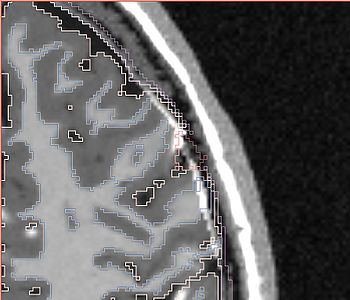

NOTE: red outlines the boundary of the label corresponding to the initial tumor seed!

All the following experiments are based on the "thin dura" input labels, and the tumor seed image shown on the right. The tumor label is shown in green color. Note that the tumor is touching the gray matter label.

The seed image can be downloaded File:Seed3.nrrd

The following screenshots capture the same axial slice (#119) of the following images in order: (1) image containing the tumor probabilities, and (2) the simulated Gad enhanced image, both overlayed with the warped tumor/brain tissues labels.

Poisson ratio 0.5

(initial value)

Note very very minimal deformation of the surrounding brain tissue, although the tumor volume increased, for Poisson=0.5.